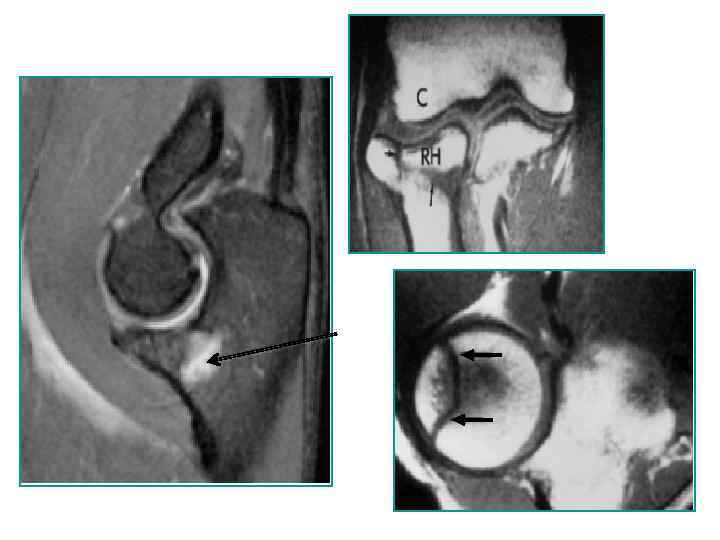

Свободное суставное тело в ямке локтевого отростка Свободное суставное тело в ямке венечного отростка

Свободное суставное тело в ямке локтевого отростка Свободное суставное тело в ямке венечного отростка